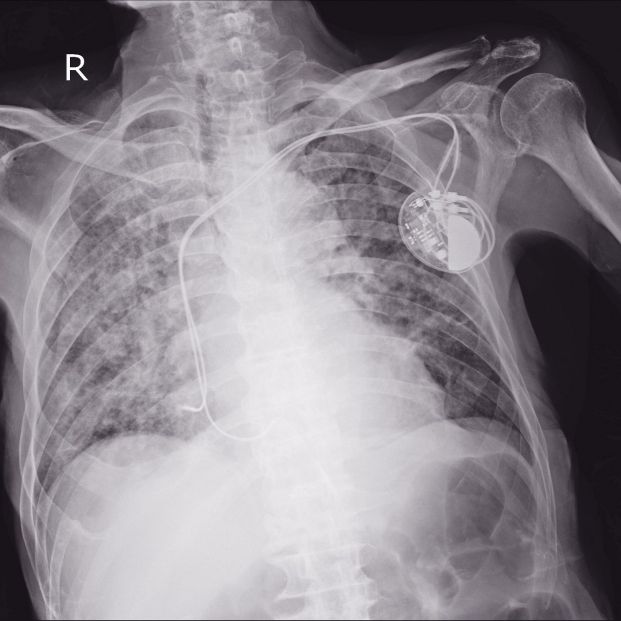

Los que son permanentes se tienen que implantar subcutáneamente. Se colocan próximos a la clavícula. En el caso de necesitar un solo electrodo se ubica en el ventrículo derecho, pero si son necesarios dos, el segundo se situará en la aurícula derecha. Después se tienen que conectar al marcapasos. El cable se tiene que introducir a través de una vena cercana hasta donde se vaya a colocar definitivamente, y una vez terminado el proceso se deberá verificar que está en el sitio correcto por medio de rayos X. Así quedará situado definitivamente bajo la piel y por último se cerrará la incisión.